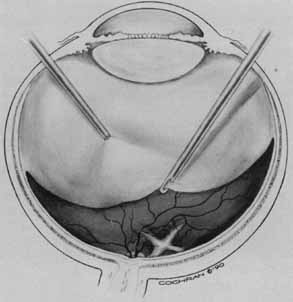

Tissue surgically peeled from the macular region in cases of impending macular hole has been found to be clinically consistent with posterior hyaloid. This finding was supported by electron microscopic examination of the tissue (Fig. 4).13,36 This observation is supported by the work of Kishi and Shimizu.37 They noted a large, optically empty space that appeared to be a complete posterior vitreous detachment in eyes with advanced liquefaction of the vitreous. They termed this area the posterior precortical vitreous pocket (PPVP). They found this pocket in 48 of 84 eyes with either an incomplete or no posterior vitreous detachment, and in 19 of 36 eyes with a posterior vitreous detachment. They noted that in eyes with advanced liquefaction of the vitreous, a large PPVP appeared to be a complete posterior vitreous detachment. In all of their postmortem cases, the posterior layer of the PPVP was found to be a thin layer of cortical vitreous. The presence of this PPVP strengthens the hypothesis that contraction of remaining attached cortical vitreous causes tangential traction on the macula, which gives the clinical appearance of an idiopathic macular cyst or hole.13,25,26,38 These impending holes or cysts' have been noted to resolve with spontaneous or surgical stripping of the membranes.13,25

Vitreous surgery for macular holes has been refined over the last few years. A standard three-port core vitrectomy is performed. The posterior hyaloid is detached from the retina with the vitrectomy instrument switched to suction mode, at a level of 200 mm Hg. The vitrector port is then placed near the nasal edge of the optic nerve and suction is applied. The posterior hyaloid is engaged and the vitrector tip is pulled anteriorly to promote a posterior hyaloidal separation. A hyaloidal separation is only achieved when a Weiss ring is visualized. After successful detachment of the posterior hyaloid, a more peripheral vitrectomy is performed to provide maximal space for gas tamponade.

An air–fluid exchange is performed with the aid of a soft-tipped cannula. Confirmation of posterior hyaloidal separation can be determined at this time. The soft-tipped cannula is placed near the optic nerve and suction is applied. If the tip engages residual hyaloid, it will bend toward the retina in a fishhook fashion. If residual hyaloid is noted, the vitreous cavity is refilled with fluid and another attempt is made to separate the posterior hyaloid. After the air fluid exchange is completed, 5 to 15 minutes are allowed to elapse for fluid reaccumulation resulting from surface tension. The residual fluid is removed with the soft-tipped cannula and the sclerotomies are trimmed free of vitreous and closed. The air in the vitreous cavity is exchanged with either 16% C3F8 or 20% SF6. The patient is instructed to remain in a face-down position for up to 14 days.